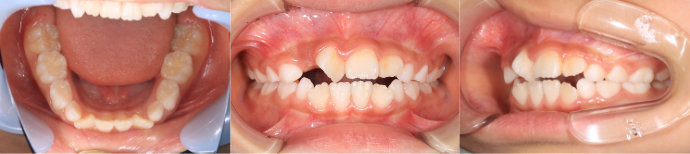

| Case2 |

| 出っ歯 |

| <治療前> |

| <治療後> |

| 主訴 |

上の前歯が出ている |

| 診断名 |

上顎前突 |

| 年齢 |

8歳 |

| 使用装置 |

マルチブラケット装置/ヘッドギア |

| 抜歯部位 |

永久歯の抜歯は無し |

| 治療期間 |

3年6か月 |

| 治療費概算 |

検査・診断料:5万円+税 装置・技術料:25万円+税 来院ごとの処置・管理料:5,000円+税 保定装置料:5万円+税 |

| リスク・副作用 |

特になし |